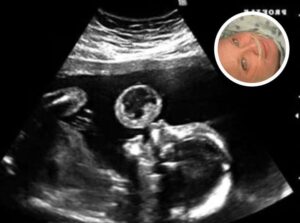

Tammy Gonzalez, a Miami mother, went in for what she expected to be a routine prenatal ultrasound, but the appointment quickly turned into a moment of fear and uncertainty. Doctors discovered a large, bubble-like mass hovering above her unborn baby’s mouth, something no parent expects to see during a joyful first glimpse. Confused and terrified, Gonzalez asked whether the growth was on her or her baby, hoping for clarity as doctors examined the strange image.

Further evaluation revealed the mass was a teratoma, a rare and potentially fatal tumor that affects roughly 1 in 100,000 pregnancies. The diagnosis came with devastating warnings: the tumor could cause miscarriage, threaten the baby’s survival, and potentially put Gonzalez’s own health at serious risk. The medical advice was straightforward—termination of the pregnancy was recommended.